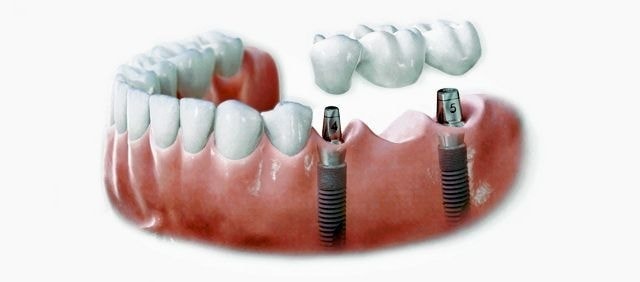

インプラントとは、顎の骨に人工歯根となる金属を埋め込み、その金属を土台にして、天然の歯と同じような人工の歯を取り付ける治療方法です。

埋め込む金属に生体との親和性が高いチタンが使われる事が多く、チタンは長年の臨床研究でインプラントの素材として最も安全であり、また顎の骨としっかり結合することが確認されています。

天然歯のような見栄えだけでなく、これまでの入れ歯やブリッジでは満足することが難しかった「食べる・話す」という機能も回復できます。

インプラントは周りの歯を傷つけず、残った歯への影響が少ないため、自分の歯を多く残せます。